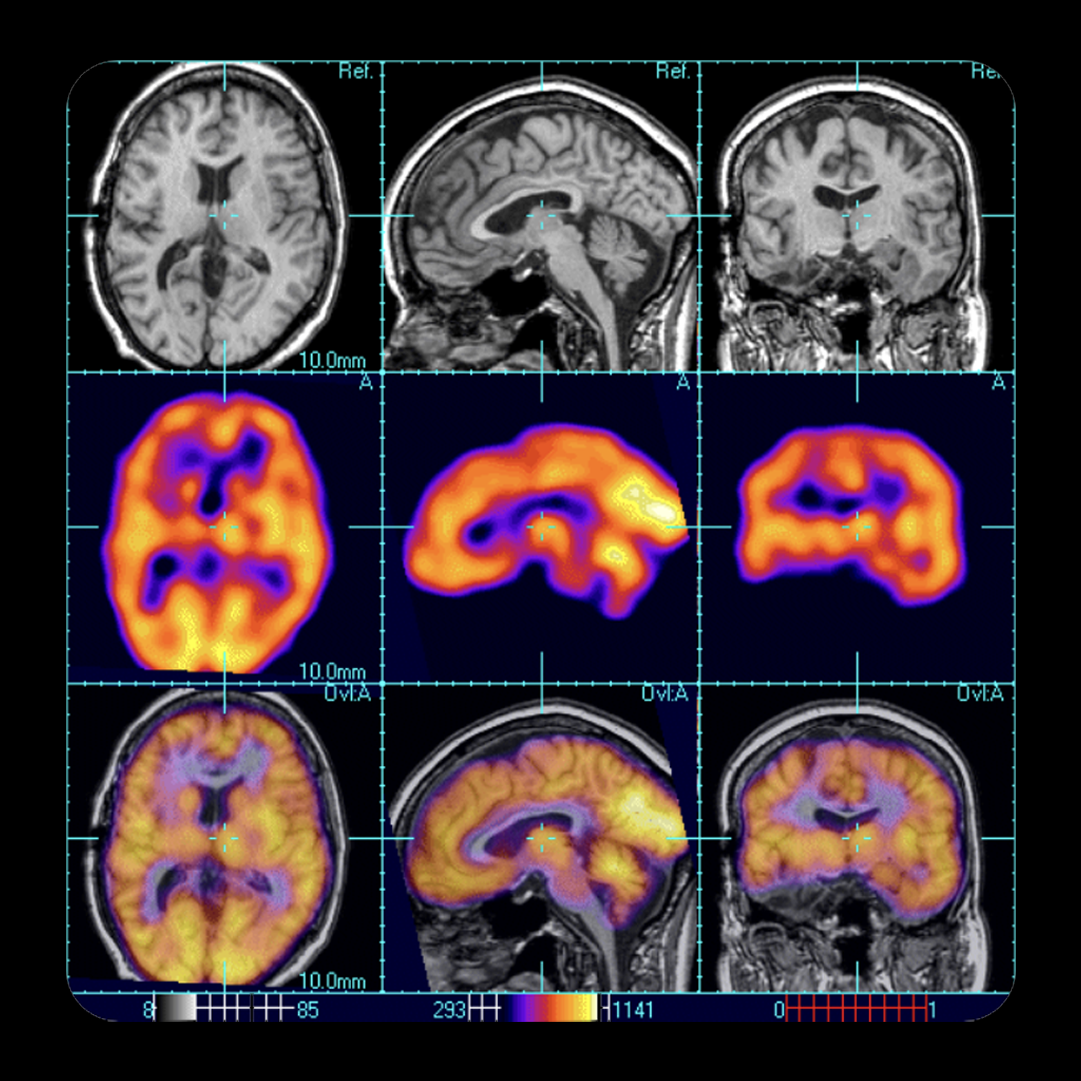

- Full suite of in vivo CNS imaging modalities: PET, SPECT, MRI, CT, BLI, FMRI, cryofluorescence tomography (CFT)

- Quantitative biomarker imaging for target engagement, neurotransmitter release, and volumetric brain analysis

Neurotransmitter & Brain Activity Mapping

Measure neurotransmitter release, metabolism, and functional brain changes using PET, MRS, and autoradiography.

Structural & Volumetric Imaging

Assess treatment impact on brain morphology with high-resolution MRI, DTI, and segmentation- based volumetric analysis.